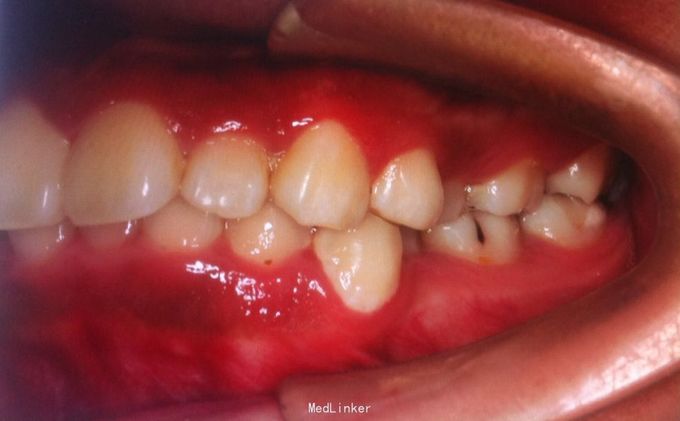

恒牙期 左侧磨牙中性关系,右侧远中关系 前牙三度深覆合 上合牙列中度拥挤,下颌重度拥挤 下颌中线偏右 关节有弹响

安氏二类,牙列拥挤 拔牙矫治,拔除14、24、34、44,强支抗,排齐整平上下牙列,矫治后磨牙中性关系,前牙覆合覆盖正常,面型略改善